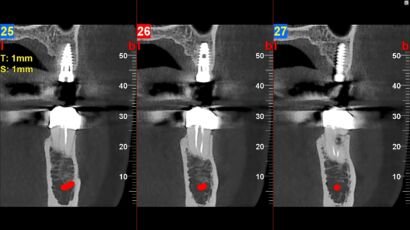

El Tac dental maxilar, también conocido como tomografía computarizada de haz cónico (CBCT, por…